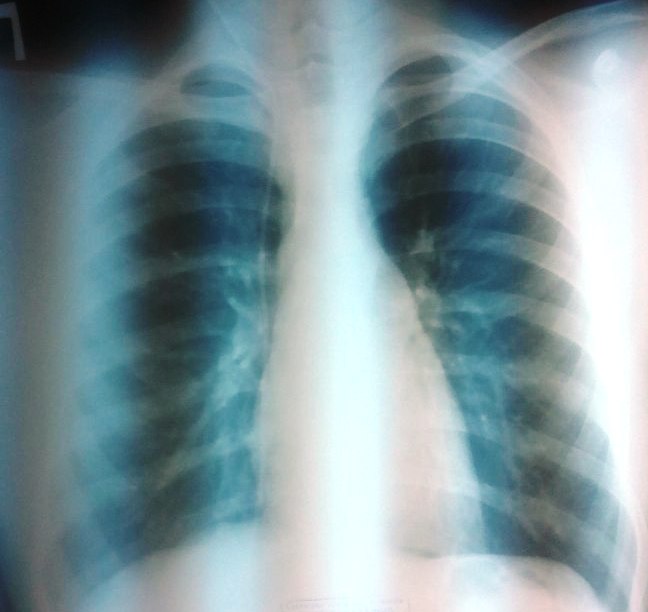

Вентрикуло-перитонеальный шунт: Показания и применение

Раздел: Фотоальбом решений